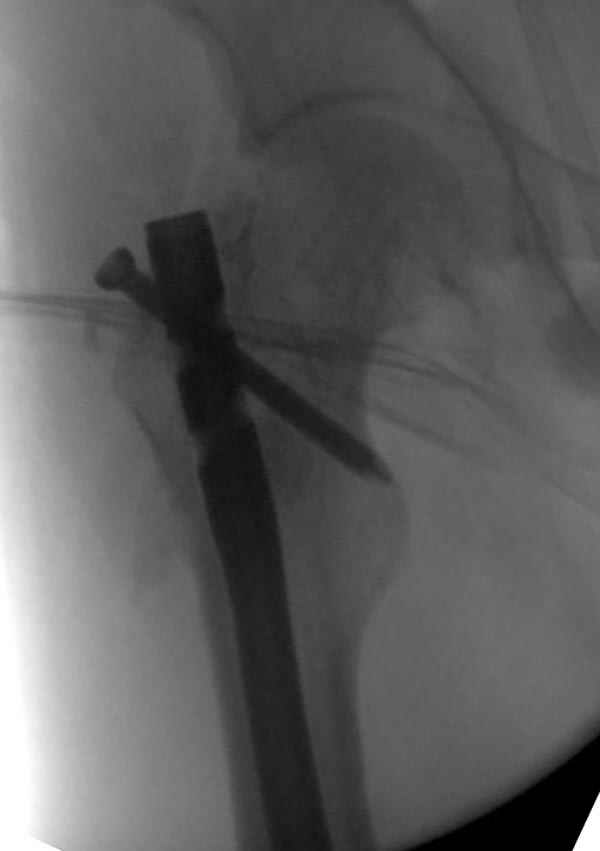

Рутинный интрамедуллярный остеосинтез с расверливанием и с фиксацией реконструктивным трокантерик штифтом (рис №1, №2),

Замена реконструктивного штифта “Custom made Nail” с антибиотиком (рис №5, №6),

после промывки канала с рассверливанием внутреннего кортекса, через 4 недели антибиотический штифт удалили, оспалителный процесс остановлен и бедро сросся.